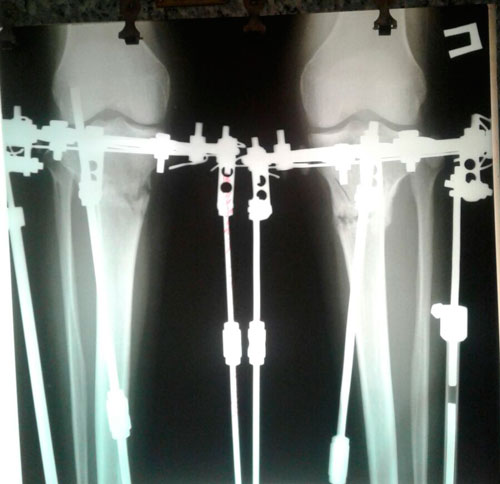

Дата операции 06.07.2017г.

Дата снятия аппаратов 05.10.2017г.

Срок лечения 90 дней.

Наталья, можете выложить сюда последний рентген? 90 дней